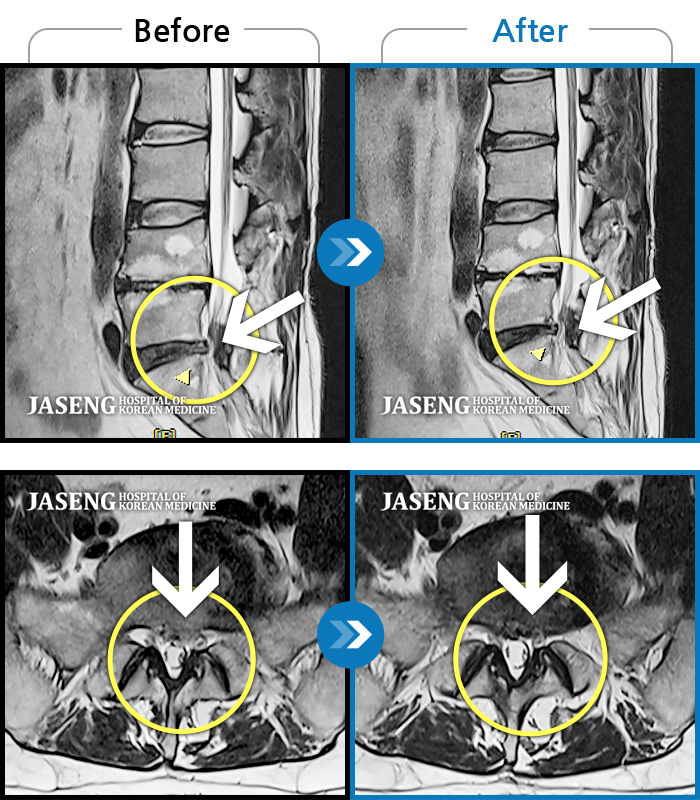

허리디스크

도움받은 사례

광주 · 장영우 원장

양측 허리의 묵직한 통증 및 기침 시 증상이 심화되어 내원하셨습니다.

촬영시기

2024.12.09 ~ 2025.05.24

2025.06.05